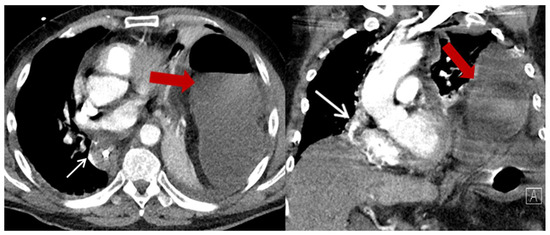

| Characteristics | HH (n = 23) (%) |

| Content of HH, n (%) | |

| Colon | 23 (100) |

| Additionally small bowel | 3 (13) |

| Position of the HH n (%) | |

| Left thoracic side | 18 (78.3) |

| Right thoracic side | 1 (4.4) |

| Both sides | 1 (4.4) |

| Lower mediastinum | 3 (13) |